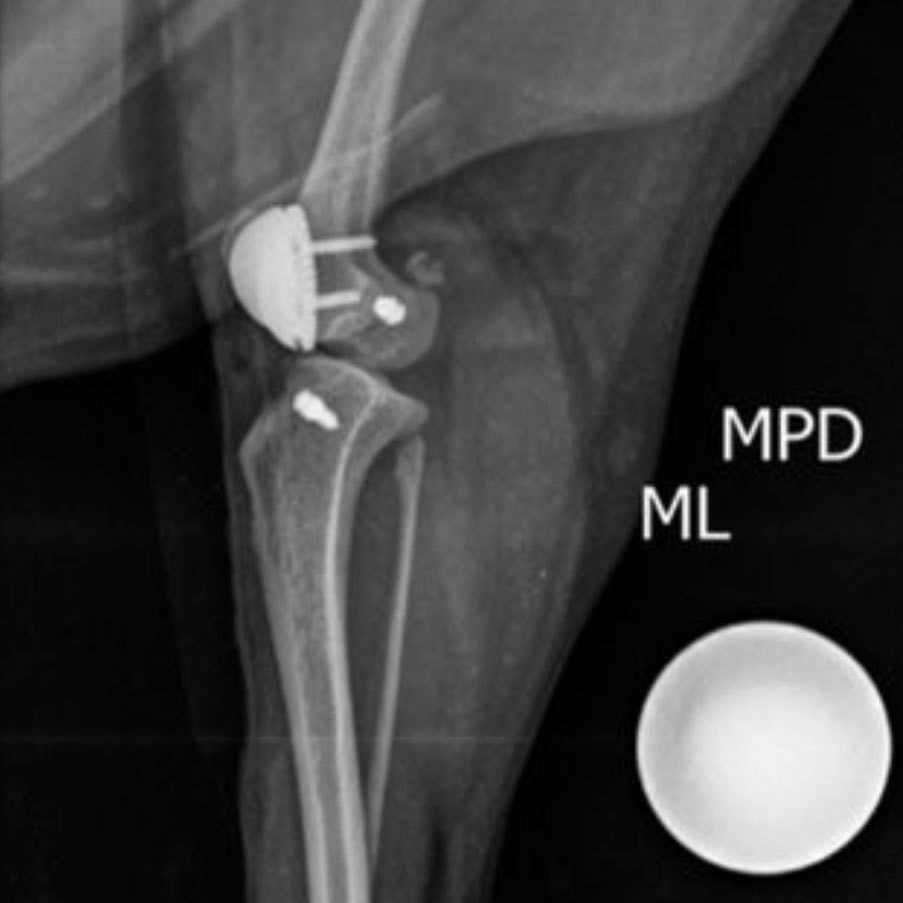

Ruptura de Ligamento Cruzado

Doença degenerativa do joelho de caes que pode ser incapacitante se nao tratada logo.

Luxação de

Patela

Resultado de mal alinhamento da perna, é a “rótula” (patela) fora do lugar. É confênira e quanto antes for tratada melhores os resultados.